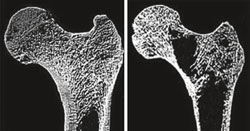

![]() | Intakte und aufgelöste innere Knochenstruktur Bilder mit freundlicher Genehmigung von Dr. Ego Seeman, Seeman E and Delmas PD. N Engl J Med 2006; 354: 2250-2261 |